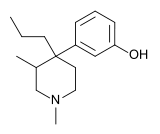

| Opioid peptides | Skeletal molecular images |

|---|---|

| Adrenorphin |  |

| Amidorphin |  |

| Casomorphin | |

| DADLE | |

| DAMGO |  |

| Dermorphin | |

| Endomorphin |  |

| Morphiceptin |  |

| Nociceptin |  |

| Octreotide |  |

| Opiorphin |  |

| TRIMU 5 |  |